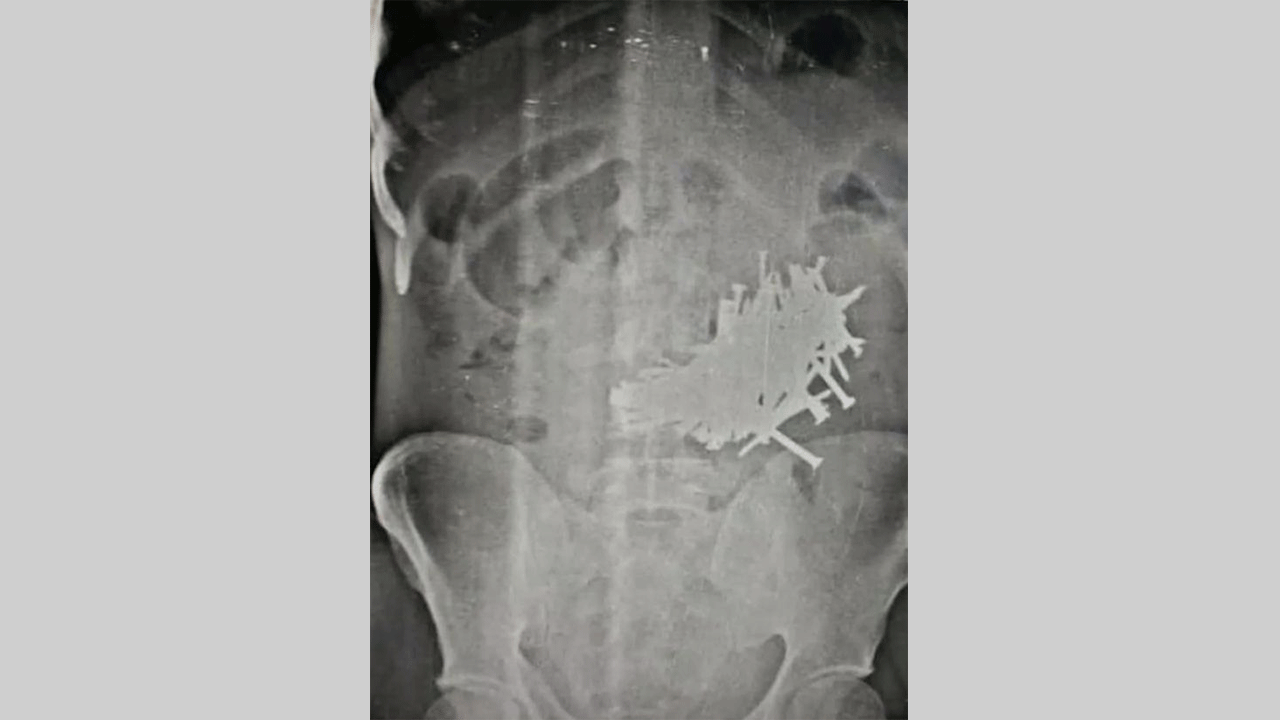

أطباء يخرجون 116 مسماراً من معدة رجل في الهند

نجا رجل من الموت بعد أن أزال الأطباء أكثر من 100 من المسامير الحديدية من معدته.

واشتكى الرجل البالغ من العمر 43 في الهند من آلام في المعدة، وعثر الأطباء على محتويات غريبة في معدة الرجل بعد إجراء الأشعة السينية.

وقال الأطباء في مستشفى بوندي الحكومي إنهم اخرجوا 116 مسمارا على الأقل، يبلغ طول كل منها ستة سنتيمترات ونصف.